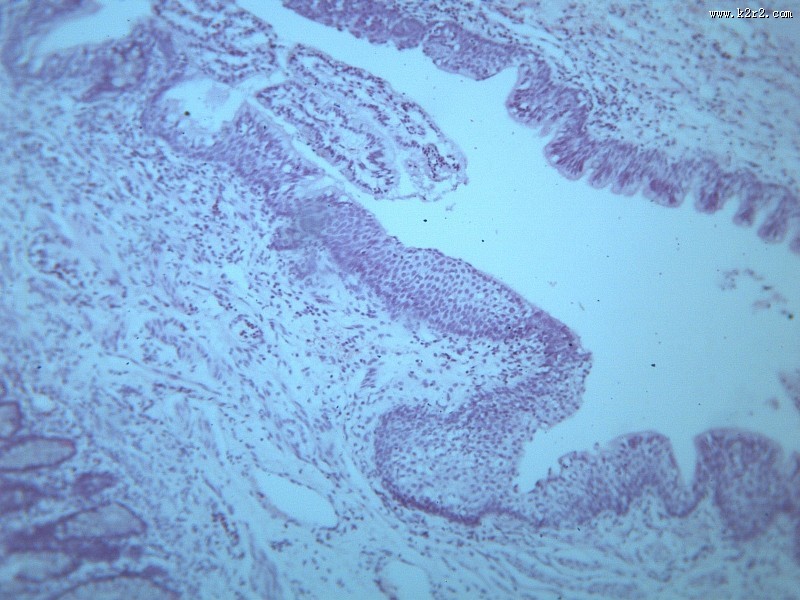

首页 > 其他类别 > 畸胎瘤(12张) > 畸胎瘤 第5张

畸胎瘤 - 第5张